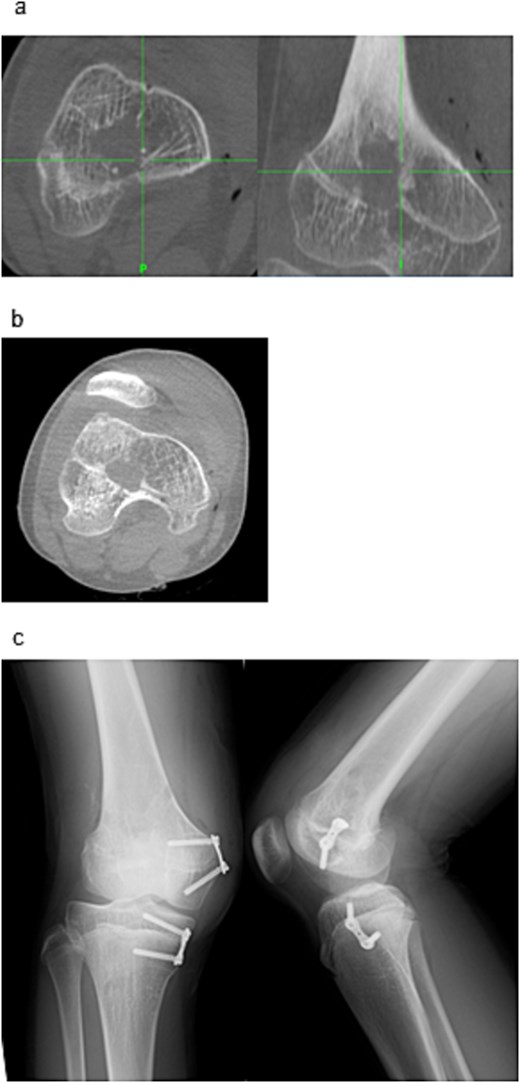

Two 1.6 mm Kirschner wires were inserted percutaneously from the medial and lateral distal femoral sides toward the bar (Fig. 2e), and 8 mm drill portals were created along the wires (Fig. 2f). A 4 mm arthroscope (Stryker Corporation, Kalamazoo, MI, USA) was introduced through one portal for direct visualization of the physeal bar (Fig. 2g). A Stealth-Midas™ high-speed drill (Medtronic) was advanced through the contralateral portal. Resection was performed under concurrent navigational and endoscopic monitoring (Fig. 3a and b). Complete bar removal was confirmed visually and on the navigational display (Fig. 3c). Intraoperative CT via O-arm confirmed a thorough excision (Fig. 4a) with no cortical perforation (Fig. 4b).

Endoscopic and navigational views during resection. (a) Physeal bar resection was performed using a high-speed drill under navigation guidance. (b) The physeal bar (arrow) was directly visualized endoscopically. (c) Following excision, residual growth cartilage (arrow) was observed at the site.

Post-resection imaging and implant placement. (a) Post-resection CT confirming complete removal of the physeal bar. (b) No evidence of cortical perforation was seen. (c) Postoperative radiographs (anteroposterior and lateral) showing placement of the eight-plate across the distal medial femur and proximal medial tibia.